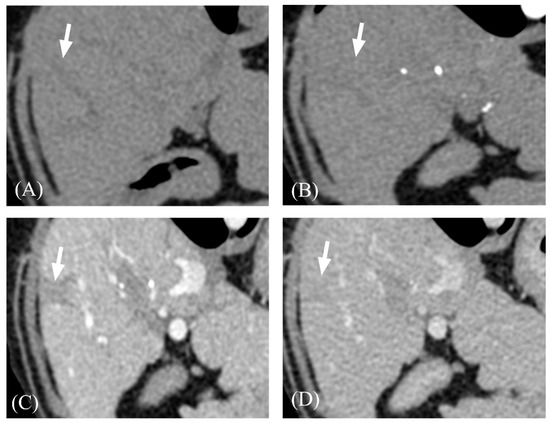

| Transient hepatic attenuation difference | Present | 7/13 (53.8%) | 4/8 (50%) | 3/5 (60%) | 1.000 |

| Absent | 6/13 (46.2%) | 4/8 (50%) | 2/5 (40%) |

- Yamasaki, M.; Furukawa, A.; Murata, K.; Morita, R. Transient Hepatic Attenuation Difference (THAD) in Patients without Neoplasm: Frequency, Shape, Distribution, and Causes. Radiat. Med. 1999, 17, 91–96. [Google Scholar]

- Colagrande, S.; Centi, N.; Carmignani, L.; Salvatori Politi, L.; Villari, N. Meaning and Etiopathogenesis of Sectorial Transient Hepatic Attenuation Differences (THAD). Radiol. Med. 2003, 105, 180–187. [Google Scholar]

- Choi, B.I.; Chung, J.W.; Itai, Y.; Matsui, O.; Han, J.K.; Han, M.C. Hepatic Abnormalities Related to Blood Flow: Evaluation with Dual-Phase Helical CT. Abdom. Imaging 1999, 24, 340–356. [Google Scholar] [CrossRef]

- Yu, J.S.; Kim, K.W.; Sung, K.B.; Lee, J.T.; Yoo, H.S. Small Arterial-Portal Venous Shunts: A Cause of Pseudolesions at Hepatic Imaging. Radiology 1997, 203, 737–742. [Google Scholar] [CrossRef]